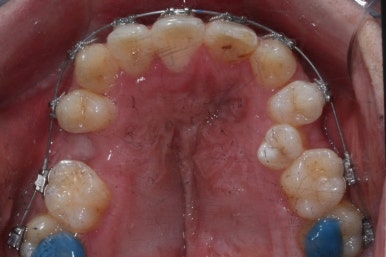

악궁확장이 시작될 시점과 악궁확장을 다 진행했을 시점의 비교입니다.

확실히 좁아져 있던 가로 넓이가 넓어진 것을 볼 수 있습니다.

악궁확장장치는 바로 제거할 경우 다시 원상태로 폭이 좁아질 수 있으므로 3~6개월은 유지해야 합니다.

적절한 시기가 되면 악궁확장장치를 제거하고, 확장장치가 걸려있던 치아도 가지런하게 해줍니다.

윗니는 아직 가지런하게 하는 작업 중이며, 아랫니는 가지런하게 하는 작업은 거의 다 되었습니다.